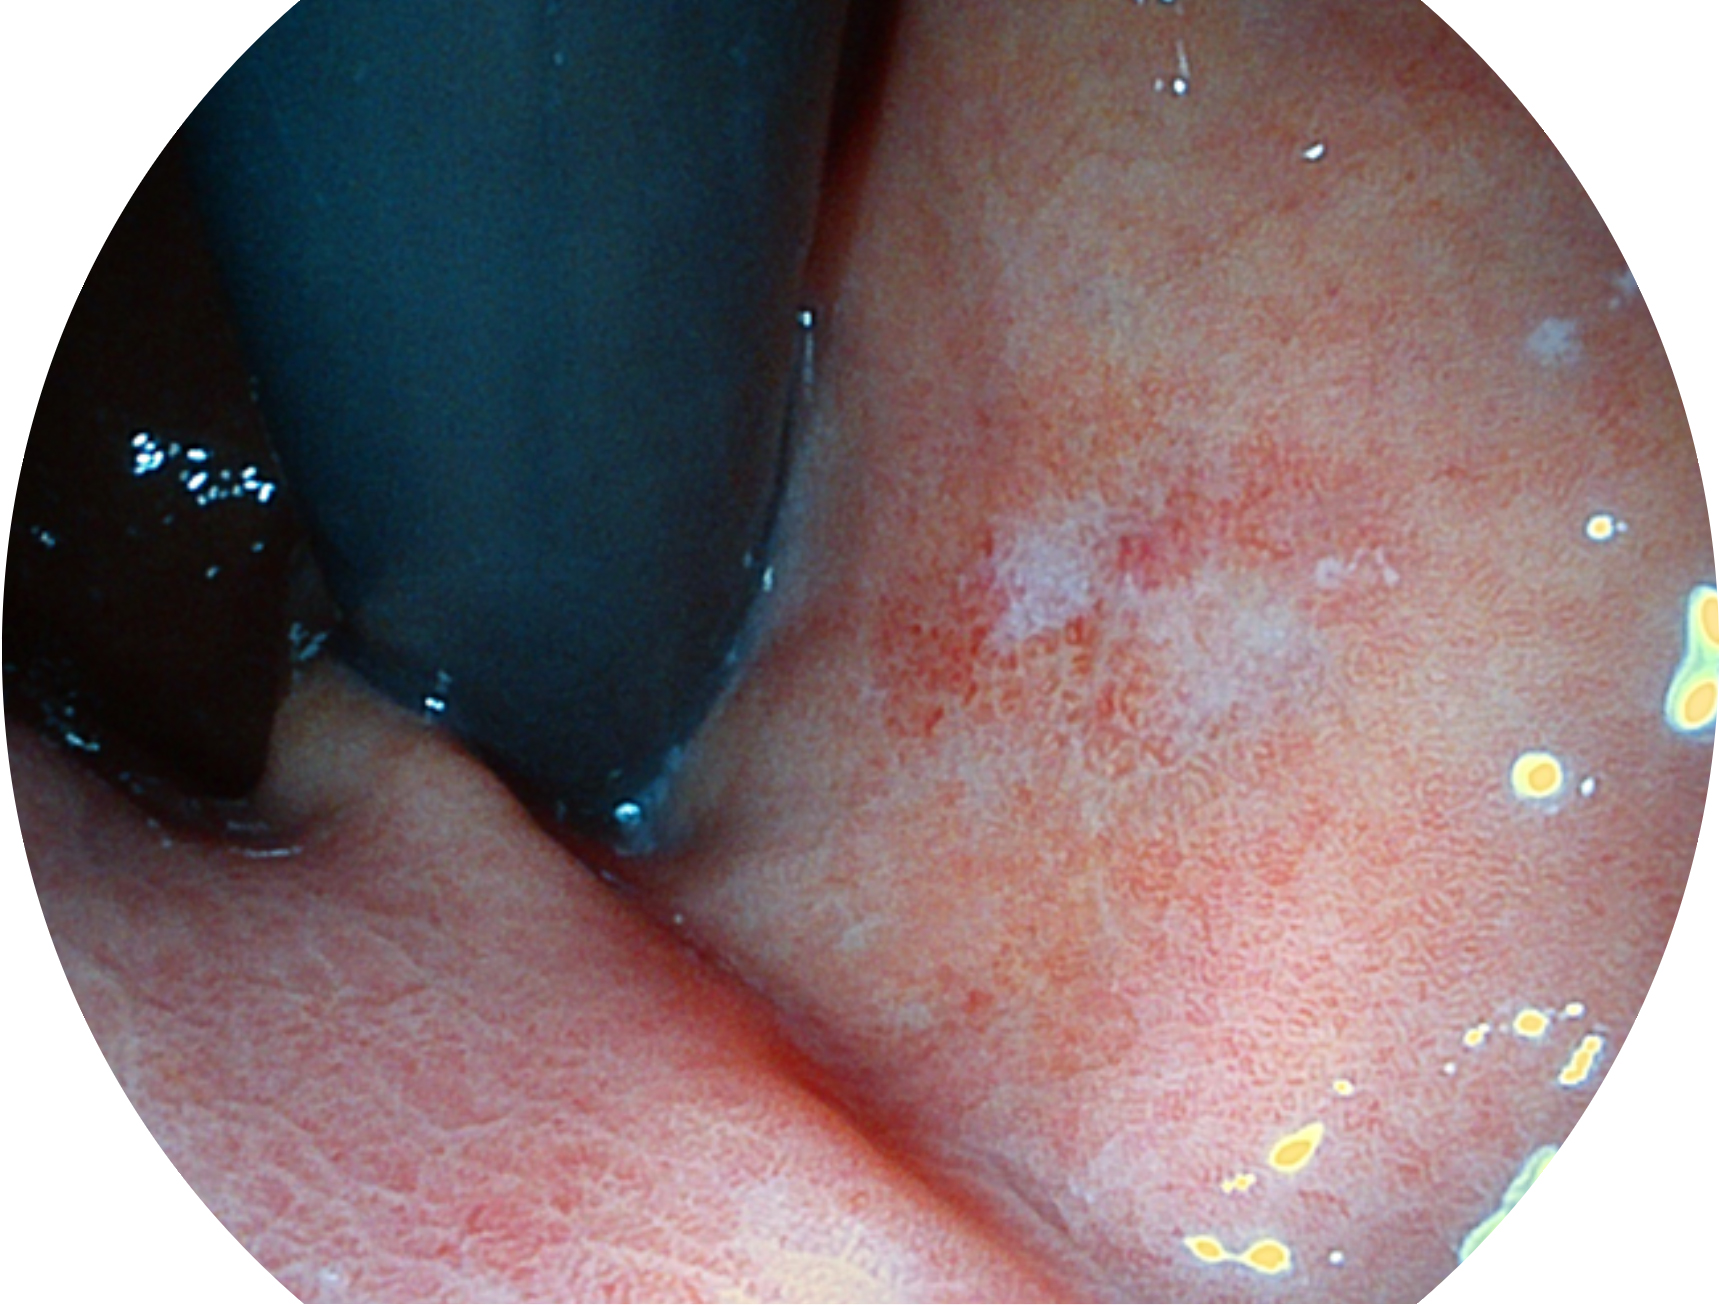

美狮贵宾会官网新开发的内镜染色技术,主要是基于多波长LED 光源的开发,VLS-55Q 四波长LED 光源是由四个不同颜色的LED光按照相应照明模式所规定的特定发光比例进行合束后形成,合束后形成的照明光的光谱由红光、绿光、蓝光及蓝紫光这四个不同的波段范围构成。具有更高光谱自由度,通过光谱比例的控制,实现了聚谱成像技术,英文全称为“Spectral Focused Imaging, SFI”,缩写为“SFI”和光电复合染色成像技术,英文全称为“Versatile Intelligent Staining Technology, VIST”,缩写为“VIST”。